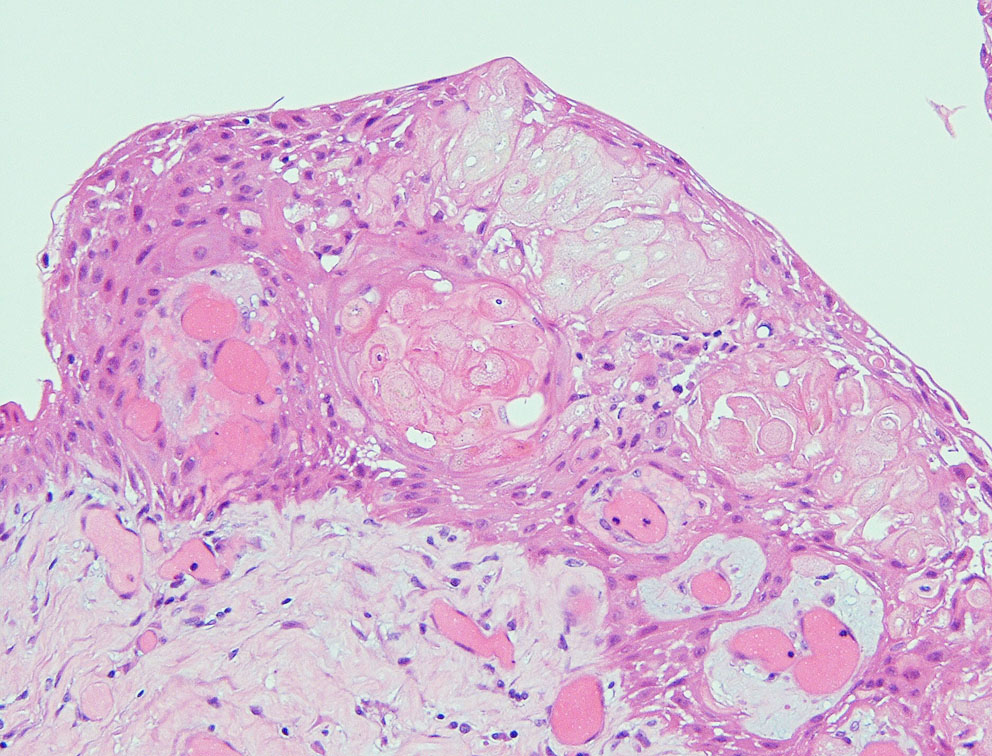

Adamantinomatous craniopharyngioma showing well-differenciated squamous epithelium including whorl of squamous cells. MIB-1 index of the dense basal layer was approximately 10%.

Xanthogranulomatous part in an adamantinomatous craniopharyngioma showing cholesterol clefts (upper left) surrounded by collagen tissue, dense macrophage infiltration, and lymphatic infiltrates (upper right)